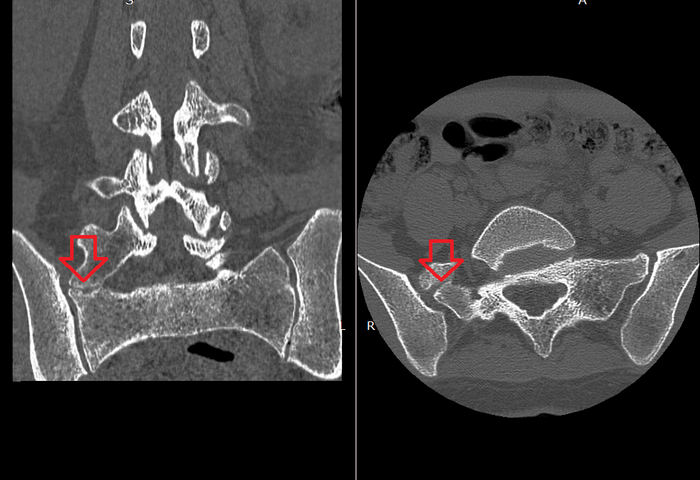

По МРТ никаких данных за эту проблему не было (хотя если бы были коронарные срезы, то можно было бы увидеть), поэтому мы выполни КТ поясничного отдела позвоночника с захватом крестца.

Как думаете, нашли мы что-то на КТ?

На КТ была обнаружена аномалия развития позвоночника в виде добавочного переходного позвонка. Вот такие бывают.

Мы видим формирование дополнительного сустава в области крестца, которого не должно быть.

Зона изысканной болезненности совпадает с проекцией этого сустава.